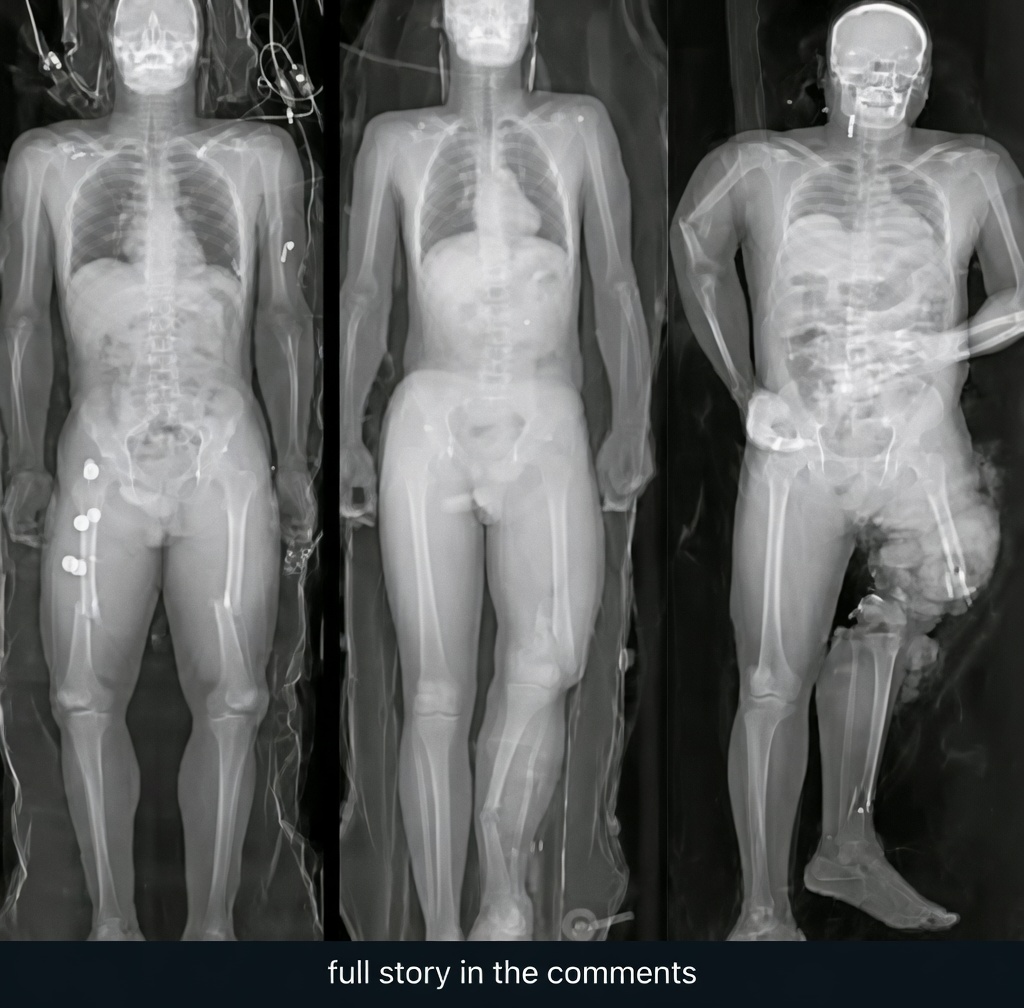

You were scrolling late at night when the image stopped you cold: a high-contrast human heart pierced by a jagged syringe, bold text warning that if you got the jab you needed to see this before it was too late. Your thumb hovered over the screen as a wave of unease washed over you, the kind that makes your own chest tighten just a little. The post had thousands of shares already, and you could not help wondering if that faint ache you felt earlier was something more.

Social media has been flooded with these haunting visuals for weeks now, each one designed to grab attention and spark instant fear. The digital landscape turned them into a new kind of psychological warfare, bypassing calm discussion and hitting straight at primal worry about health and family. You have seen friends and family share them, some with genuine concern and others with outright alarm, turning what used to be casual scrolling into moments of quiet panic.

The complication arrives when the images pair with real symptoms like chest discomfort that anyone might notice after a long day or a recent cold. What starts as a simple scroll escalates into self-diagnosis in the comments, with strangers offering terrifying interpretations that feel too close to home. The narrative shifts from awareness to alarm, leaving ordinary aches feeling suddenly ominous and urgent.

The turning point comes when you pause long enough to look past the dramatic visuals and seek context from reliable medical sources. Practical insight reveals that while rare heart-related side effects were documented in early vaccine data, they were overwhelmingly mild and far less common than similar risks from the virus itself. Doctors consistently emphasize that any chest pain deserves professional evaluation rather than social-media interpretation.

You learn that these viral graphics are often stock or AI-generated images paired with cherry-picked or outdated information, crafted to maximize engagement rather than deliver balanced facts. This approach bypasses the nuance that real medicine demands, turning complex health data into simplified scare tactics that spread faster than measured discussion ever could.

The climax hits when you realize the hidden truth these posts rarely mention: the images are not presenting new evidence or official warnings but are instead fueling anxiety for clicks and shares. Medical experts note that most people who experience mild chest symptoms after vaccination or infection recover fully, and the greatest risk often comes from ignoring symptoms instead of getting checked promptly by a doctor.